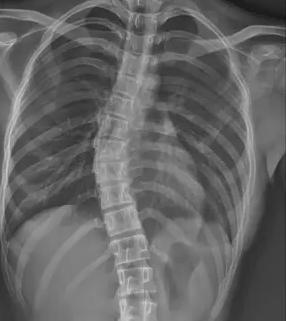

當(dāng)前青少年脊柱側(cè)彎診療體系面臨系統(tǒng)性困境。在篩查環(huán)節(jié),傳統(tǒng) X 線測(cè)量 Cobb 角雖為金標(biāo)準(zhǔn),但輻射風(fēng)險(xiǎn)限制其大規(guī)模應(yīng)用;現(xiàn)有初篩手段假陽性率高達(dá) 35%,而低輻射智能篩查技術(shù)在基層醫(yī)院普及率不足 12%,導(dǎo)致大量病例漏診。疾病管理鏈條存在顯著斷層,Cobb 角<10° 的輕癥患者因缺乏標(biāo)準(zhǔn)化干預(yù)方案,錯(cuò)失黃金矯正期。保守治療領(lǐng)域,支具治療依從性不足 40%,定制精度誤差超 15%,全國注冊(cè)矯形師缺口達(dá) 83%;物理治療資源配置失衡,70% 的基層醫(yī)療機(jī)構(gòu)尚未建立規(guī)范康復(fù)訓(xùn)練體系。

針對(duì)上述痛點(diǎn),醫(yī)療科技企業(yè)與科研機(jī)構(gòu)正聯(lián)合構(gòu)建智慧防治體系。迪納醫(yī)療研發(fā)的全幅 Dira-DUC 技術(shù),通過 AI 輔助三維重建實(shí)現(xiàn)單次 0.02mSv 低劑量成像,較傳統(tǒng)設(shè)備輻射量降低 87%。其自主研發(fā)的脊柱側(cè)彎風(fēng)險(xiǎn)預(yù)測(cè)模型,整合 120 萬例臨床數(shù)據(jù),可精準(zhǔn)識(shí)別高危人群,篩查準(zhǔn)確率提升至 92%。診療環(huán)節(jié)引入智能 Cobb 角測(cè)量算法,將人工測(cè)量誤差從 ±5° 壓縮至 ±1.2°。在支具治療方面,智能監(jiān)測(cè)支具內(nèi)置壓力傳感器與物聯(lián)網(wǎng)模塊,實(shí)時(shí)反饋佩戴數(shù)據(jù)并生成個(gè)性化調(diào)整方案。物理治療領(lǐng)域,標(biāo)準(zhǔn)化訓(xùn)練課程已納入國家衛(wèi)健委基層康復(fù)指南,配備 AI 動(dòng)作捕捉系統(tǒng)的智能訓(xùn)練艙正在全國 127 家縣級(jí)醫(yī)院推廣。